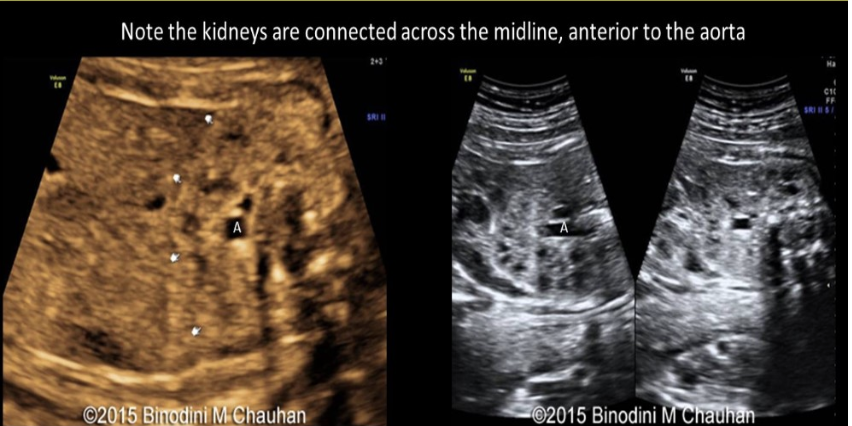

an abn of renal fusion where the lower pole of kidneys are connected across the midline of abd called

a) horseshoe kidney

b) epispadias

c) cross fused renal ectopia

d) persistent cloaca